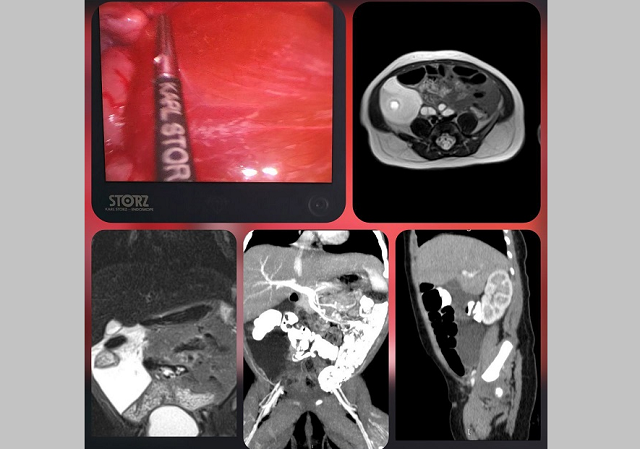

Врачи хирургического отделения для детей раннего возраста ДРКБ выполнили малоинвазивную операцию для удаления лимфатической мальформации у новорожденного младенца. Об этом сообщает пресс-служба клиники.

Ребенка госпитализировали после ультразвукового исследования во время медицинского осмотра с подозрением на кисту в брюшной полости. Специалисты отделения хирургии детей раннего возраста после комплексного обследования подтвердили редкую аномалию развития лимфатических сосудов в брыжейке толстой кишки.

Заведующая отделением, кандидат медицинских наук Мария Зыкова и врач-детский хирург Буй Вьет Анх выполнили малоинвазивную операцию — лапароскопическое удаление лимфатической мальформации с сохранением сосудов брыжейки толстого кишечника.

Сообщается, что данный случай является крайне редким, так как чаще всего подобные образования обнаруживаются в области шеи и подмышечных впадин. Согласно статистике, такие патологии встречаются примерно в четырех случаях на 100 000 госпитализаций.

Послеоперационный период прошел без осложнений, после курса лечения в клинике ребенок был выписан домой.